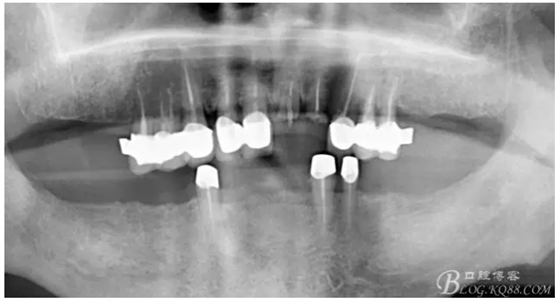

還要有足夠的牙本質(zhì)肩領(lǐng),大家現(xiàn)在可以看到患者的下頜套筒冠還是非常好的

雖然牙根折斷了,但是從這張片子可以看出我們的套筒冠還是很堅挺的,有牙齦的退縮,但是牙槽骨致密程度非常好,值得欣慰